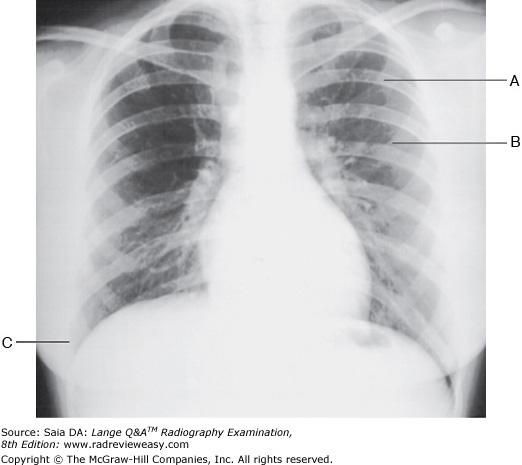

B 2 only

-The patient is well positioned; the spinous processes and sternum are seen clearly without superimposition. Adequate penetration and long-scale contrast are present without excessive receptor exposure. The patient had been shielded properly for the PA projection, but the shield was not moved to the correct location prior to the lateral exposure.